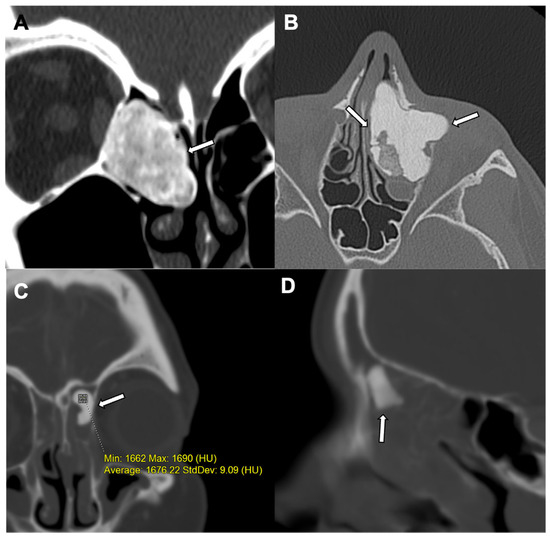

3. Osteoma

| Lesion Location | Paranasal sinuses, mainly frontal and ethmoidal | Axial skeleton (spine, pelvis, and ribs); long bones | Long bones, mainly femur | Spine and long bones |

| Radiographic/CT features | Juxtacortical, well-circumscribed homogenous sclerotic lesion | Homogenous intra-medullary sclerotic focus with spiculated margins | Small (less than 2 cm) cortical lucency with extensive surrounding sclerosis | Expansile large (more than 2 cm) lucent lesion with matrix mineralization |